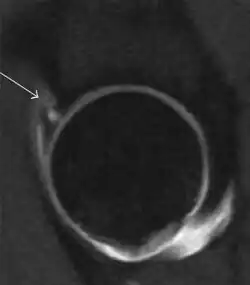

Synovial chondromatosis can be confidently diagnosed by X-ray when calcified cartilaginous chondromas are seen. However, other synovial proliferative processes, such as pigmented villonodular synovitis, require MRI for accurate diagnosis, although noncalcified synovitis can be suspected in radiographs by indirect signs, such as soft tissue swelling and/or erosions in the femoral head, femoral neck, or acetabulum (Figure 7).[1]

Figure 7:

-

Axial CT image of pigmented villonodular synovitis eroding the posterior cortex of the femoral neck.[1] -

Sagittal T2* gradient echo image showing a posterior soft tissue mass with hypointense areas secondary to hemosiderin deposition.[1] -

X-ray of synovial chondromatosis.[1] -

CT of synovial chondromatosis.[1]

In synovial proliferative disorders, MRI demonstrates synovial hypertrophy. In the case of PVNS, characteristic foci of low signal intensity related to hemosiderin deposition are better seen on gradient echo T2* images (Figure 7). In the case of synovial osteochondromatosis, the synovial hypertrophy is accompanied by intermediate signal cartilaginous loose bodies and/or low signal calcified loose bodies.[1]